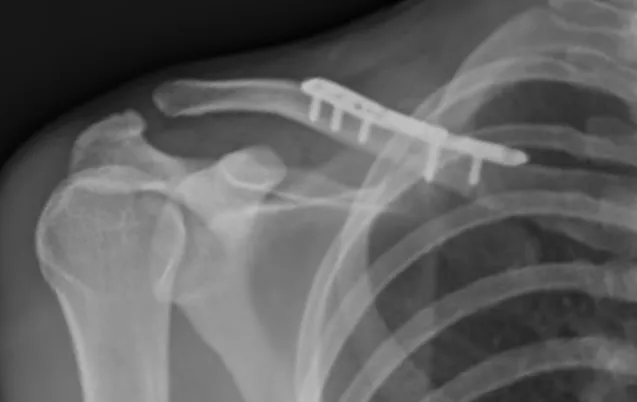

Il consiste en la réalisation d'une ostéosynthèse ; c'est à dire le repositionnement et la fixation des fragments osseux) . Cette ostéosynthèse est le plus souvent réalisée par une plaque vissée. L'intervention est réalisée le plus souvent sous anesthésie générale. une anesthésie loco-régionale est parfois associée afin de diminuer les douleurs post-opératoires. Un contrôle radiographique per-opératoire (pendant l'intervention) permet au chirurgien d'avoir un contrôle parfait du positionnement du matériel et de la qualité de la réduction chirurgicale. Après l'intervention le bras est immobilisé dans une attelle coude au corps pour une période de 4 à 6 semaines. La rééducation est généralement débutée à partir de la 4ème semaine chez un kinésitherapeute de ville. la rééducation est parfois longue et demande une étroite collaboration entre le patient et le kinésithérapeute sous le contrôle du chirurgien.

cicatrice fracture clavicule

plaque de la clavicule